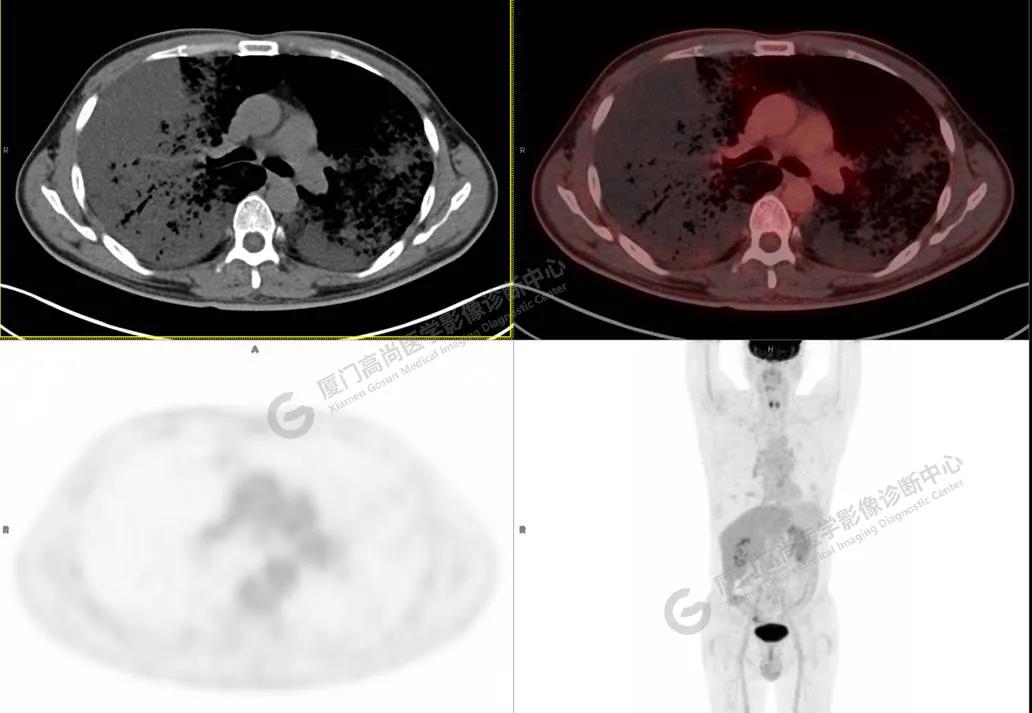

PET/CT影像圖

圖4

PET/CT所見(jiàn):雙肺大片實(shí)變影及磨玻璃影,部分呈地圖樣改變,累及右肺尖,部分放射性攝取輕微增高,SUVmax 1.77,其內(nèi)見(jiàn)多發(fā)支氣管充氣征象。

影像診斷: 雙肺大片實(shí)變影及磨玻璃影,大部分代謝不高,局部代謝輕微增高,考慮肺泡蛋白沉積癥,建議病理學(xué)檢查或肺泡灌洗物檢查。